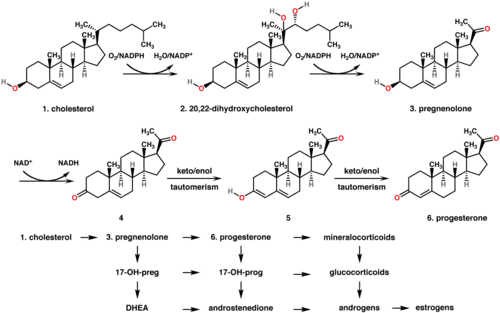

Abajo: La progesterona es importante para la síntesis de aldosterona (mineralocorticoide), así como la 17-hidroxiprogesterona lo es para el cortisol (glucocorticoide), y la androstenediona para los esteroides sexuales.

En los mamíferos, la progesterona (6), tal como todas las hormonas esteroides, se sintetiza a partir de la pregnenolona (3), que a su vez deriva del colesterol (1) (véase la parte superior de la figura a la derecha).

El colesterol (1) sufre una oxidación doble para producir 20,22-hidroxicolesterol (2). Este diol vecinal se oxida luego con la pérdida de la cadena lateral que comienza en la posición C-22, produciendo la pregnenolona (3). Esta reacción la cataliza el citocromo P450scc. La conversión de pregnenolona a progesterona tiene lugar en dos pasos. Primero, el grupo 3-hidroxilo se oxida a cetona (4) y segundo, el doble enlace se isomeriza desde C-5 a C-4, a través de una reacción de tautomerización cetona/enol[14] catalizada por la 3beta-hidroxiesteroide deshidrogenasa.

La progesterona (véase la mitad inferior de la figura a la derecha) es a su vez el precursor del mineralocorticoide aldosterona y, después de su conversión a 17-hidroxiprogesterona (otro progestágeno natural), del cortisol y la androstenediona. La androstenediona puede ser convertida en testosterona y estrona.